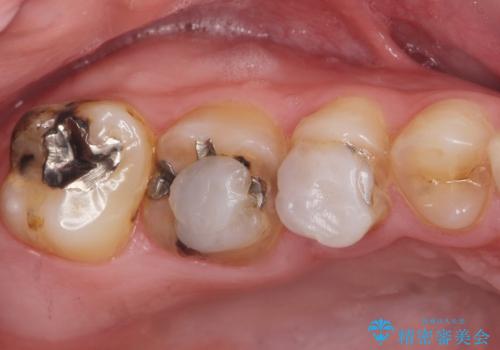

矯正を途中でやめてしまったとのことで、歯に矯正の接着材が残っており着色も顕著でした。

奥歯の咬合面にはレジンが盛られた状態でした。